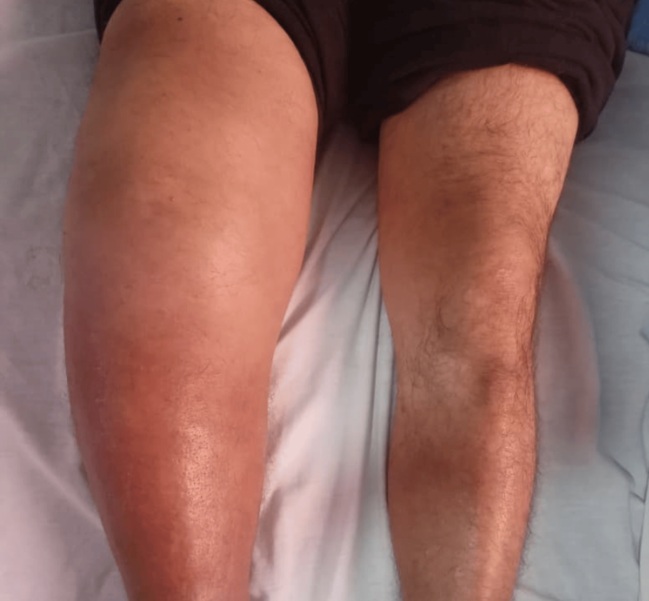

의료진에 따르면 이 62세 남성은 9개월에 결처 오른쪽 무릎에 염증이 지속된다며 병원을 찾았다. 검사 결과, 오른쪽 무릎 모양이 변형돼 있었고, 붓고, 열감이 있는 상태였지만 환자는 통증을 거의 느끼지 않고 있었다. 염증은 관절 주변 조직까지 퍼져 있는 심각한 상황이었다. 반대쪽 무릎은 정상이었다. 근골격계 초음파 사진을 찍어보니, 대량의 관절액(관절 안에 들어 있는 윤활액)이 염증 때문에 밖으로 새어 나와 있었다.

남성 역시 척수매독으로 인해 무릎 관절이 둔해졌고, 이로 인한 관절염이 생긴 것으로 의료진은 추정했다.

의료진은 항생제를 정맥에 투여하는 치료를 15일 실시해다. 약물 치료 후 염증이 줄어드는 등 증상 개선이 뚜렷했다. 다만 무릎에 심각한 구조적 손상이 있어 정형외과 치료가 논의됐고, 관절 부하 감소를 위한 보존적 치료가 진행됐다.